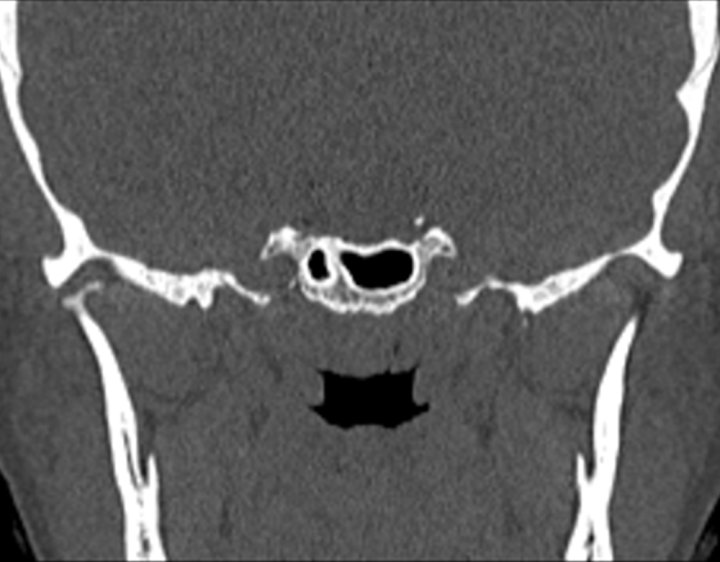

002